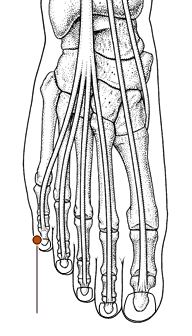

公孙穴

经穴名。出《灵枢·本输》。属足太阴脾经。足太阴之络穴。八脉交会穴之一,通冲脉。在足内侧缘,当第1跖骨基底的前下方,赤白肉际处。布有隐神经及腓浅神经分支,足背静脉网及跗内侧动脉。主治胃痛,呕吐,肠鸣,腹痛,泄泻,痢疾,腹胀,食不化,脚气等。直刺0.5-1寸。艾炷灸3-5壮;或艾条灸5-10分钟。

太白穴

经穴名。出《灵枢·本输》。属足太阴脾经。输(土)、原穴。在足内侧缘,当足大趾本节(第1跖趾关节)后下方赤白肉际凹陷处。布有隐神经及腓神经分支,足背静脉网,足底内侧动脉及跗内侧动脉的分支。主治胃痛,腹胀,呕吐,呃逆,肠鸣,泄泻,痢疾,便秘,脚气,痔漏等。直刺0.5-0.8寸。艾炷灸1-3壮;或艾条灸3-5分钟。